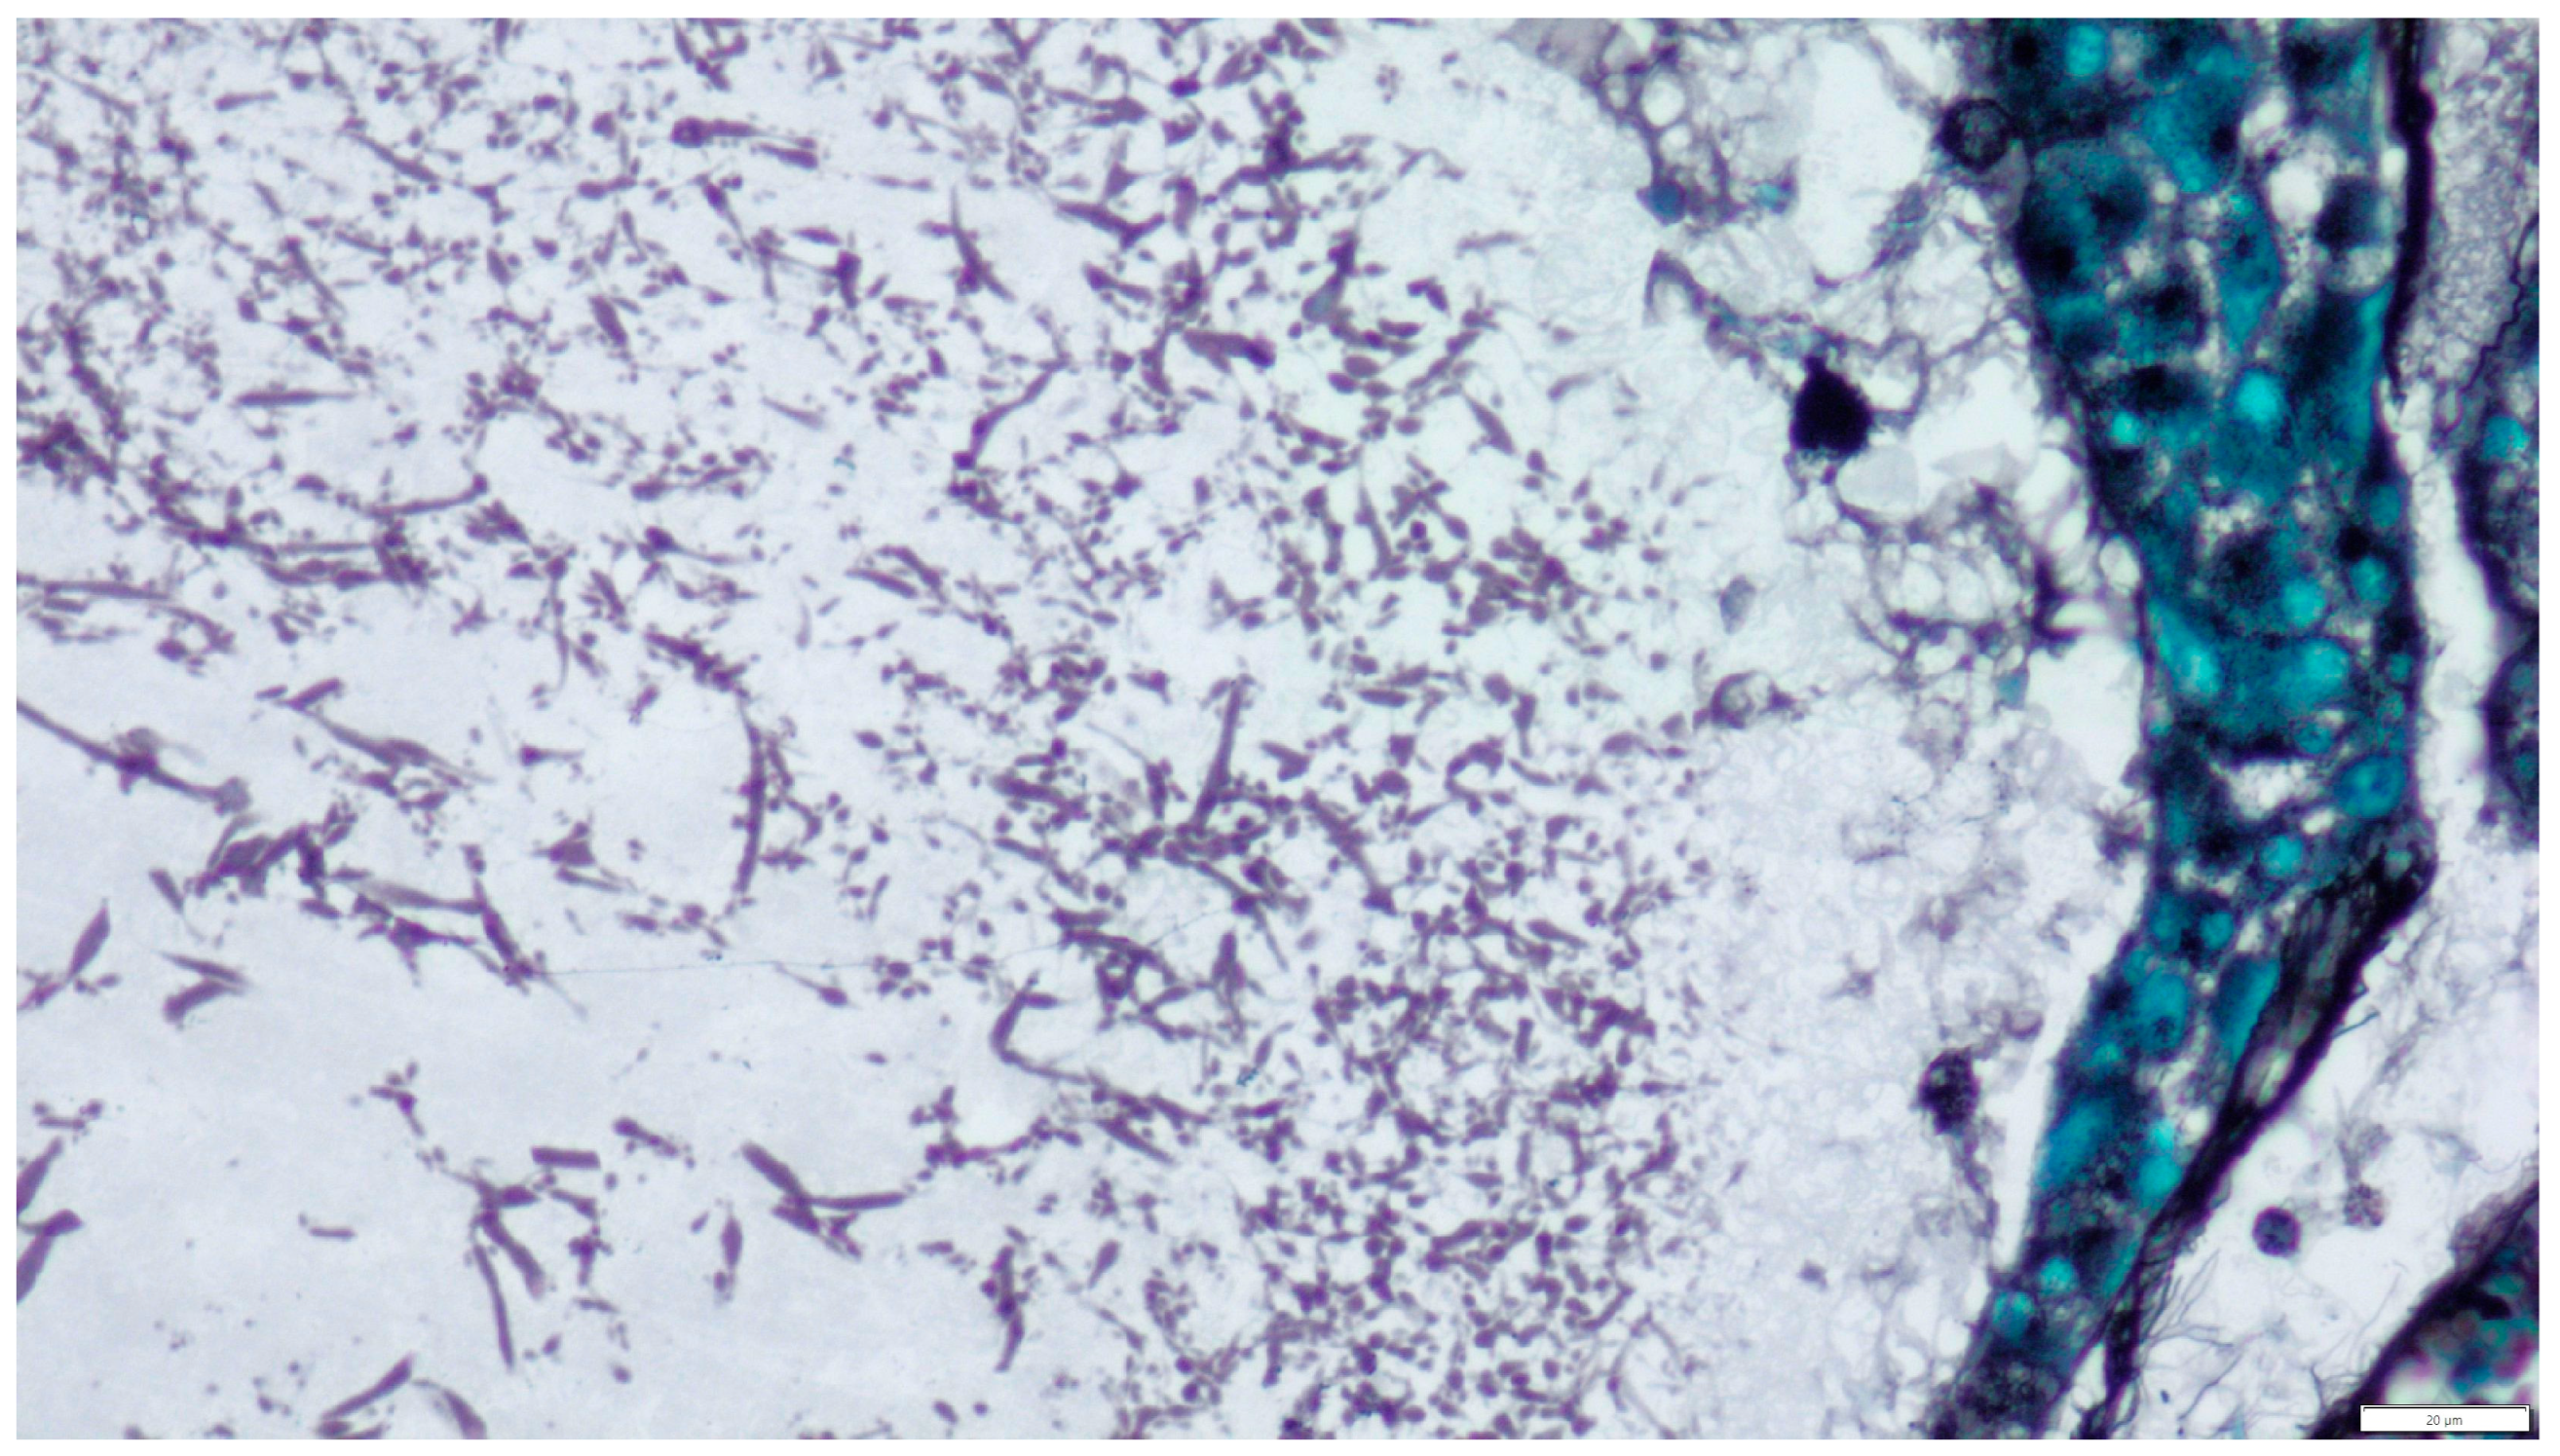

To confirm the presence of fungal structures observed on routine HE staining, Grocott staining was used. This stain highlights the fungal cell walls by staining them black and the surrounding tissues light green (Figure 5).

Figure 5.

Grocott methenamine silver (GMS) stain demonstrating septate hyphae with acute angle branching in the lumen of the cyst (magnification ×400).